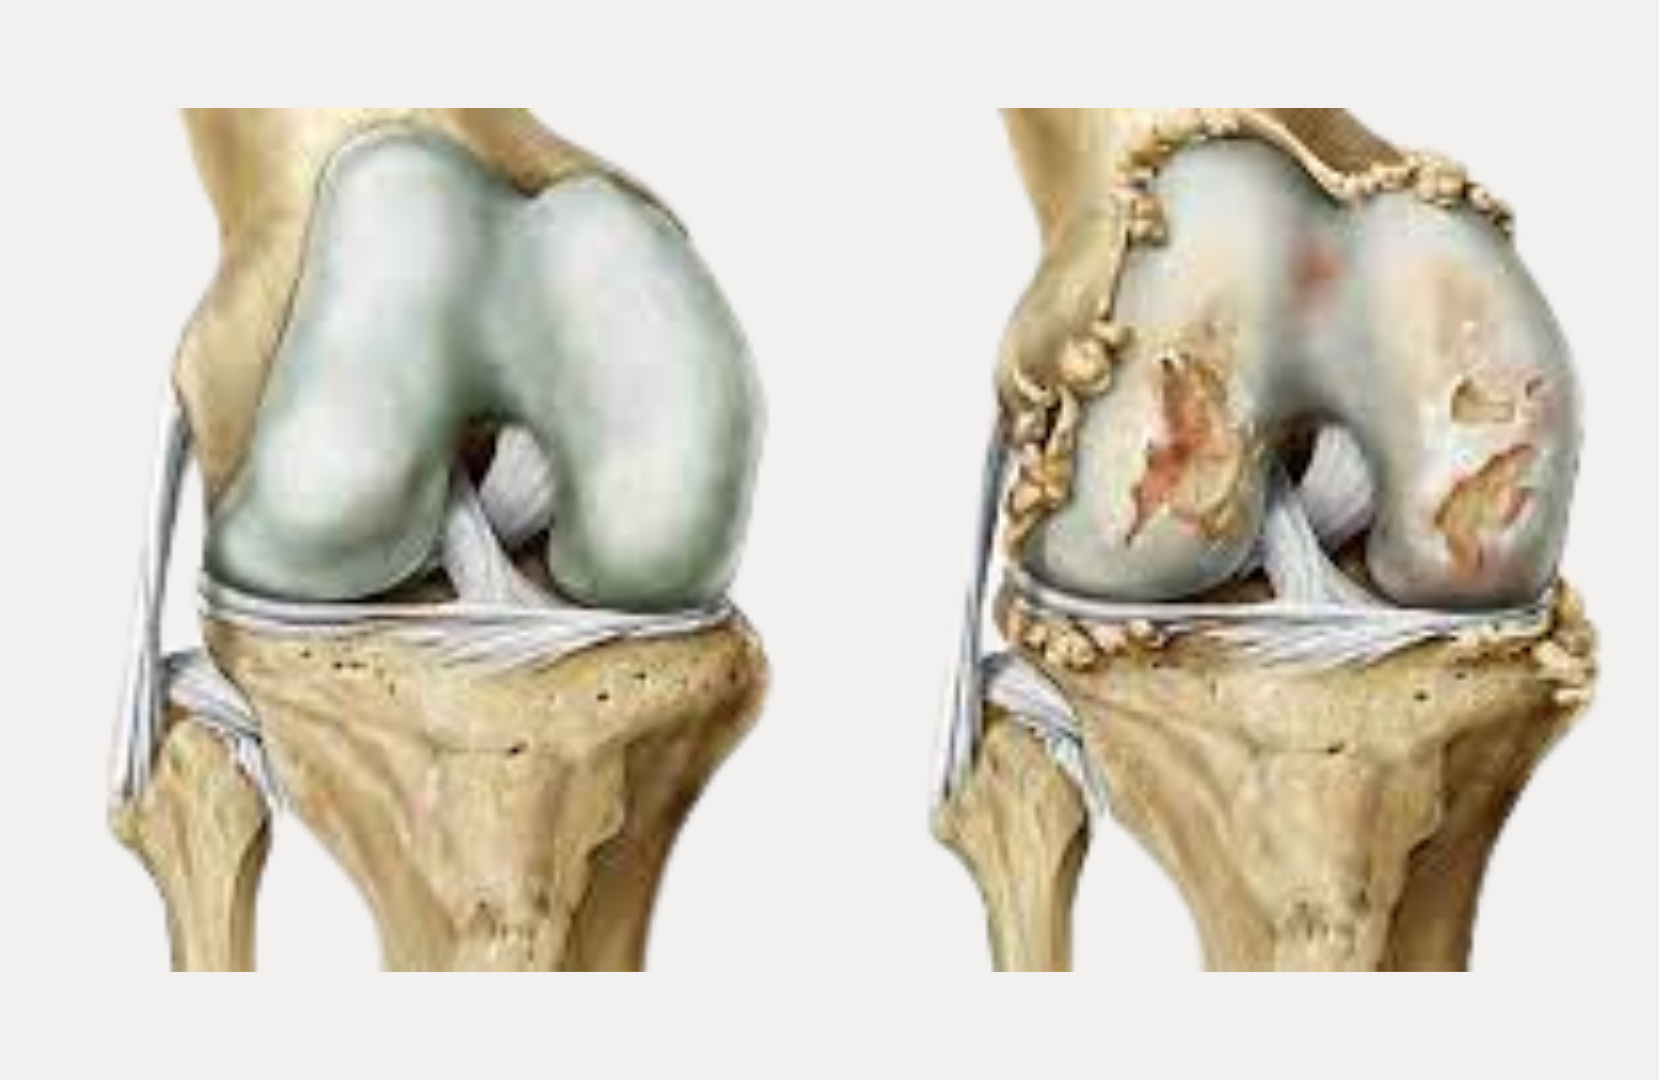

Condromalácia

O desgaste da cartilagem atrás da patela

Conheça os sinais de condromalácia, por que ela afeta tantas pessoas ativas e o que realmente funciona no tratamento (além do fortalecimento muscular).